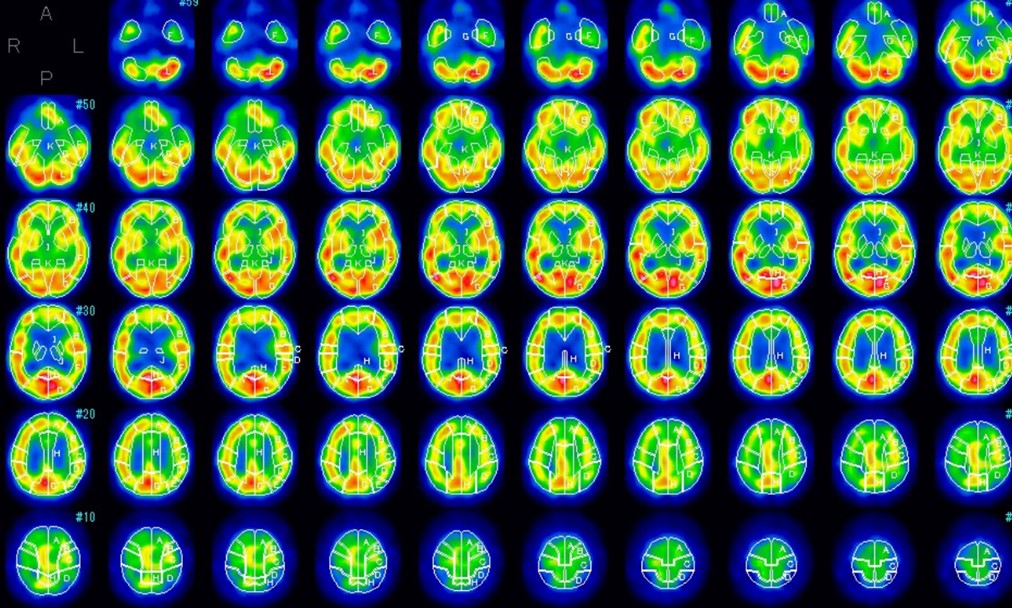

ゼノンCT

右大脳半球の血流低下が確認できます

術直後

術翌日

術直後には著明な過灌流を認めていますが、適切な治療により翌日には改善しています。